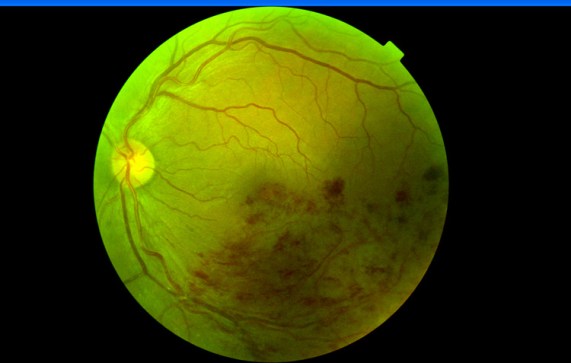

Fotografía científica: Oclusión rama venosa retina (ORVR). Rama temporal inferior

La oclusión de la vena en el cruce arterio-venoso provoca hemorragias en llamas, debido a que siguen el mismo curso de la capa de fibras nerviosas, y extravasación en capas superficiales produciendo Edema Macular Quístico.